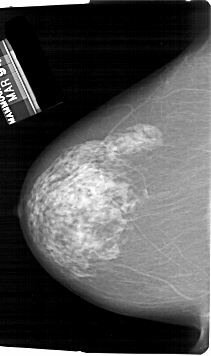

A_1829_1.LEFT_CC

LEFT_CC LINES 6751 PIXELS_PER_LINE 4006 BITS_PER_PIXEL 12 RESOLUTION 43.5 NON_OVERLAY